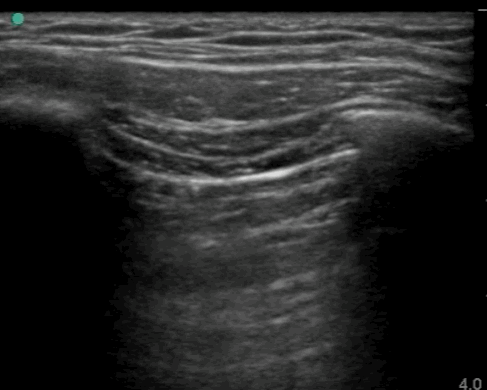

03_Lung_Posterior_axillary_Right

Normal

03_Lung_Posterior_axillary_Right – Normal